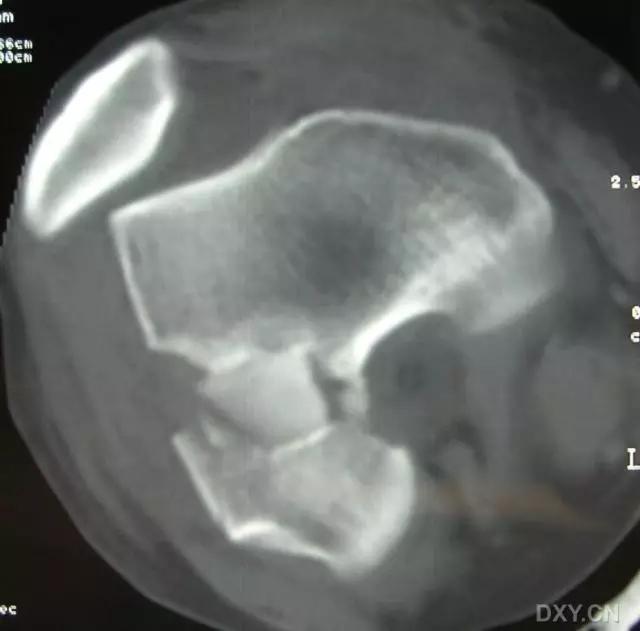

5. Hoffa 骨折

指股骨远端冠状面的骨折。

病例 1:一般股骨髁间、髁上粉碎骨折中含 Hoffa 骨折的不少见,但单纯后髁骨折则很少见。

水平位 CT

第 2 例

第 3 例